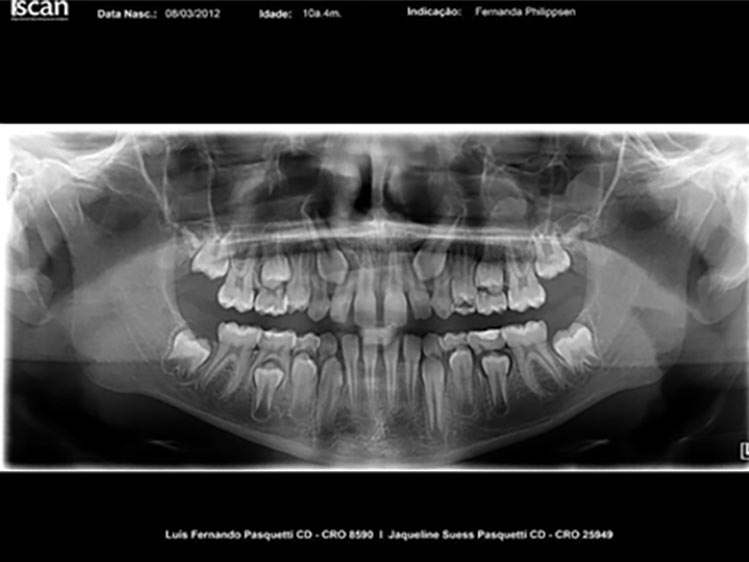

É necessário fazer uma avaliação clínica e radiográfica criteriosa da oclusão do paciente.

A primeira consulta a um ortodontista infantil deve ocorrer por volta dos 5/6 anos de idade, período que antecede as trocas dentárias.

Se o odontopediatra que acompanha a criança achar necessário, essa consulta poderá ser realizada a partir dos 3 anos.